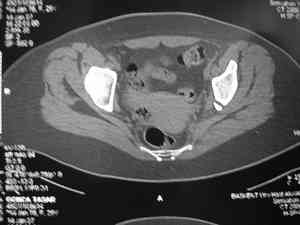

Это наблюдение 5-летней давности тогда кровопотеря составила 2,5 литра. В настоящий момент мы теряем не более 0,7-1,5 литров при одностороннем повреждении и около 2,5-3 литров тогда, когда речь идет о двусторонних повреждениях. Клинический пример.

Спасибо за клинические примеры и комментарии. Если честно то просто восхищен представлеными R-ммами (классно сделали!!!). По поводу обсуждаемого больного: конечно КТ и дополнительные R-ммы сделаем. Но хочу напомнить, что после травмы прошло более 6 лет, на сегодняшний день клинически еще и R-ки признаки нестабильности эндопротеза( как бедренного компонента так и чашки). Хочется определиться как делать в аппарате или одномоментно открыто. Лично я склоняюсь к аппаратному лечению на первом этапе.

прилагаю пример с такой же давностью травмы, репонировали аппаратом